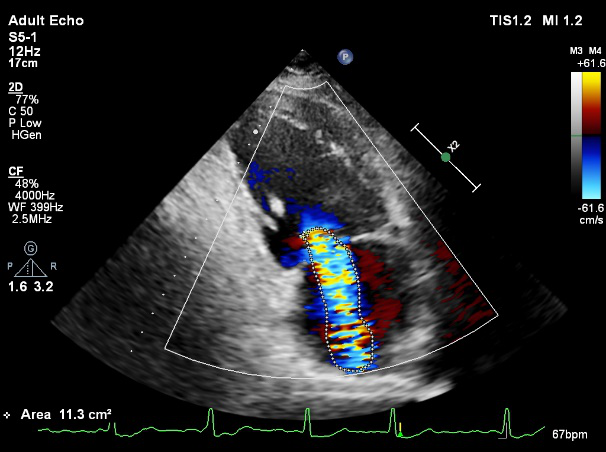

LVOT-color:MR(重度),返流面积11.3cm2

肺静脉血流频谱呈收缩期反向